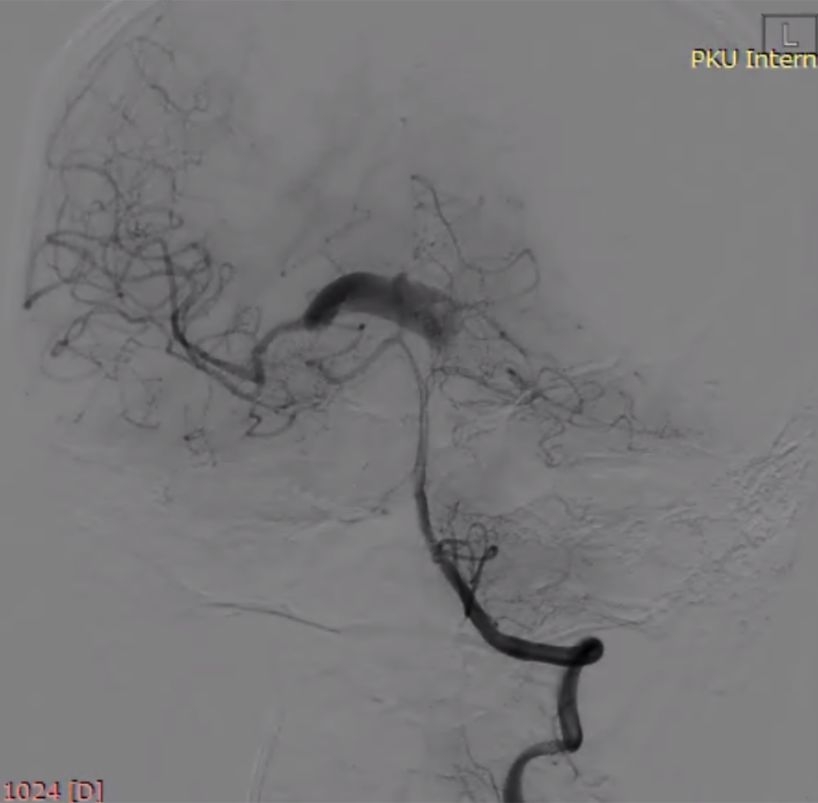

(7)支架重建后正侧位(图10)。

图10

术后复查影像(图11)。

图11